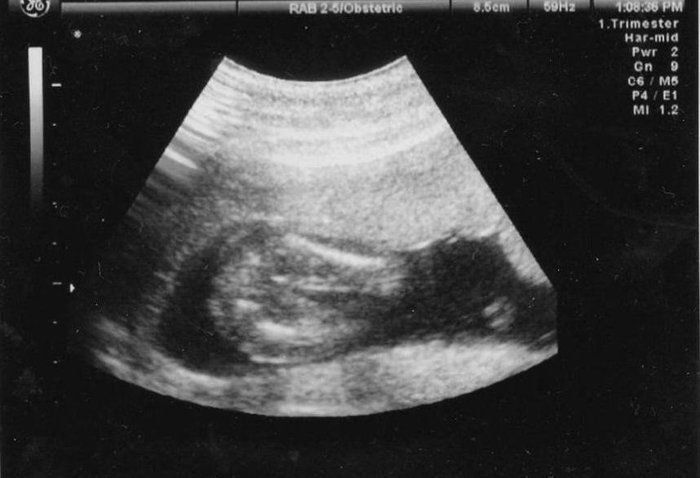

かえるさんの妊娠18週目のエコー写真

頭がくっきり。そして足を曲げている様子もわかります。5カ月目に入り、ようやくつわりがおさまりました。早速、やりたかったマタニティーヨガに挑戦。結果は、お香の匂いと逆転のポーズで吐いてしまいました。ちょっと調子に乗りすぎたようです。でも、ちょうど紅葉の季節にさしかかり、一泊旅行に出かけるなど楽しいことがたくさんできました。